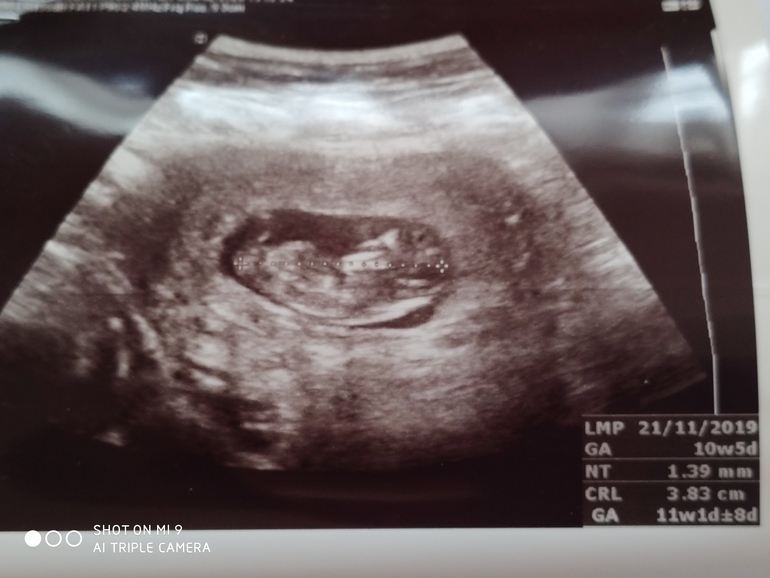

Первый скрининг. УЗИ.

Срок по месячным 10 недель 5 дней.

Результаты УЗИ:

КТР - 3,83 см, соответствует 11 неделям беременности.

Желточный мешок без патологий.

Сердцебиение ритмичное, 178 уд/мин (лучшая мелодия!!!)

Конечности - по 2.

Пуповина - 3 сосуда.

Прикрепление по передней стенке.

Толщина хориона - 12,4 мм, структура не изменена.

Гематом нет.

Околоплодные воды в нормальном количестве.

Шейка матки - 3,68 см, внутренний зев закрыт.

Цервикальный канал не расширен.

Воротниковое пространство 1,39 мм.

Носовая кость определяется.

Пороки развития не обнаружены.

Заключение: прогрессирующая беременность 11 недель, по биометрии соответствует сроку гестации, многоузловая миома матки (врач сказал, ничего делать не будем, удалим во время кесарева)

У нас все показатели в норме?? ЧСС сказал чуть повышена, но скорее всего переволновалась, умеренный тонус - назначил папаверин в попу дней пять.

Ну и фото малышика прилагаю) Не могу понять, с какой стороны голова, просветите, опытные мамочки! 🙏